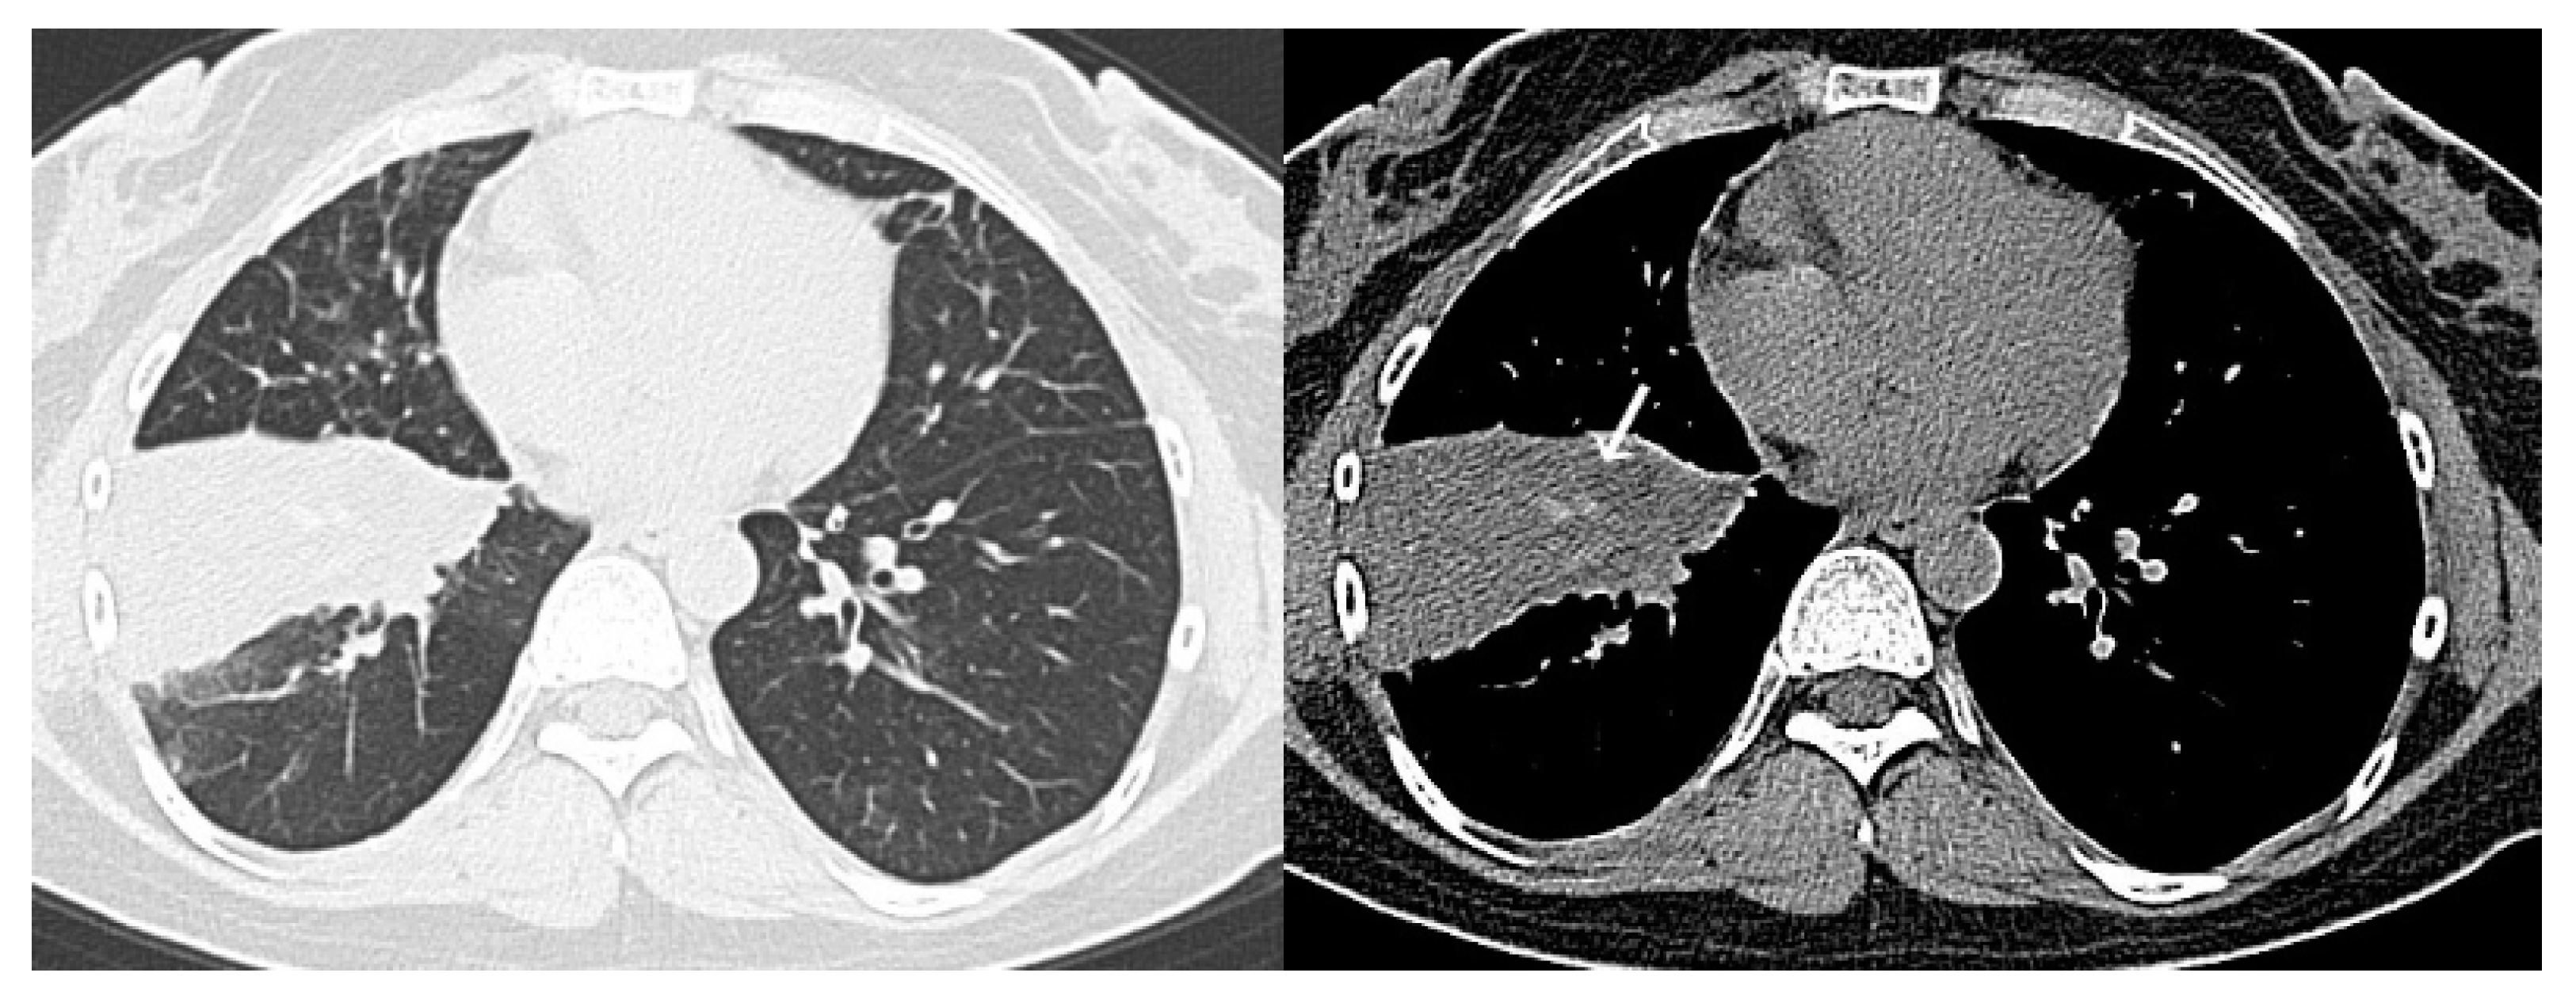

- CO-RADS 1 means a very low level of suspicion for pulmonary lesion resulting from COVID-19, based on either a normal CT or CT findings of unequivocal non-infectious etiology. Mild or severe emphysema, perifissural nodules, lung tumors, or fibrosis characterize CO-RADS 1.

- CO-RADS 2 means a low level of suspicion for pulmonary lesion resulting from COVID-19, based on CT findings in the lungs typical of etiology indicative of infections other than COVID-19, including bronchitis, infectious bronchiolitis, bronchopneumonia, lobar pneumonia, and pulmonary abscess. Findings include a tree-in-bud sign, a centrilobular nodular pattern, lobar or segmental consolidation, and lung cavitation.

- CO-RADS 5 means a very high level of suspicion for pulmonary lesion resulting from COVID-19, based on typical CT findings. Obligatory features are ground-glass opacities, with or without consolidations, close to visceral pleural surfaces, including the fissures, and a multifocal bilateral distribution.